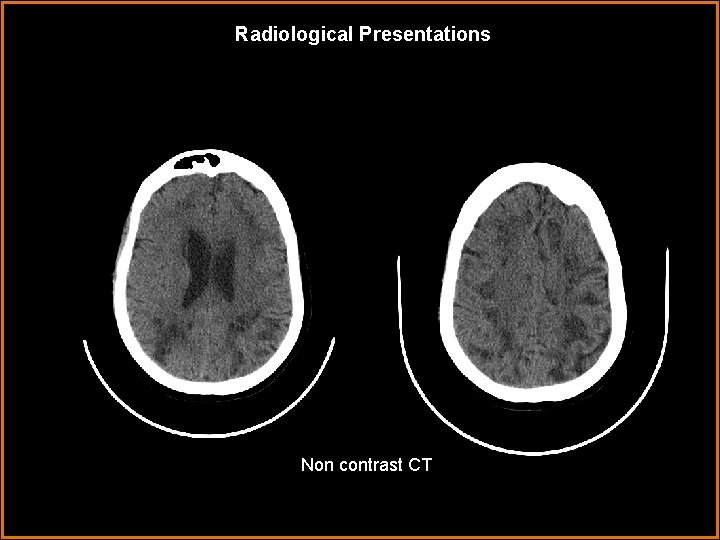

Radiological Presentations Non contrast CT

Findings and Differentials Findings: CT reveals scattered areas of hypodensity throughout the hemispheric white matter sparing the gray matter. Watershed area posteriorly involves the gray matter. Basal ganglia are spared. MRI reveals multiple, varying in size, cystic appearing lesions involving the periventricular spaces and white matter. These lesions follow CSF signal on all sequences and do not enhance. There is no restricted diffusion or blooming. On FLAIR, focal hyperintensities are seen around some of the lesions. No definite mass effect is seen. Differentials: • Mucopolysaccharidoses • Giant Tumefactive Virchow Robbins Spaces • Demyelinating Disease • Cystic Neoplasm